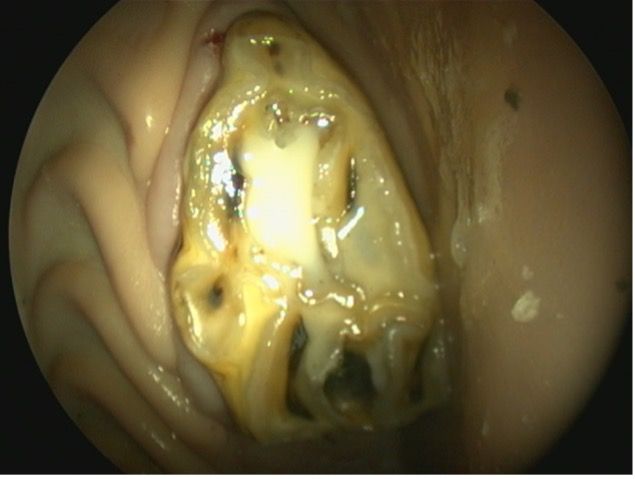

The most common type of dental caries (occlusal exposure of developmental infundibular hypocementosis) identified in equine teeth is maxillary CT infundibular cemental caries (Figure 3A). If left untreated, this can progress to septic pulpitis or pathological fracture.9 In most cases, treatment consists of debridement and filling with dental material to prevent further evolution of the tooth decay. To summarize, necrotic, impacted food material must be removed from the infundibulum using dental picks and a high-speed dental drill or burr (Figure 3B). The infundibular cavity is then flushed, and disinfectant solutions such as dilute sodium hypochlorite or chlorhexidine are flushed into the cavity preparation (Figure 3C). A layer of a single step-etch bonding product is applied to the cavity walls, and the cavity is filled with a dual-cured flowable resin composite.10-12 (Figure 3D)